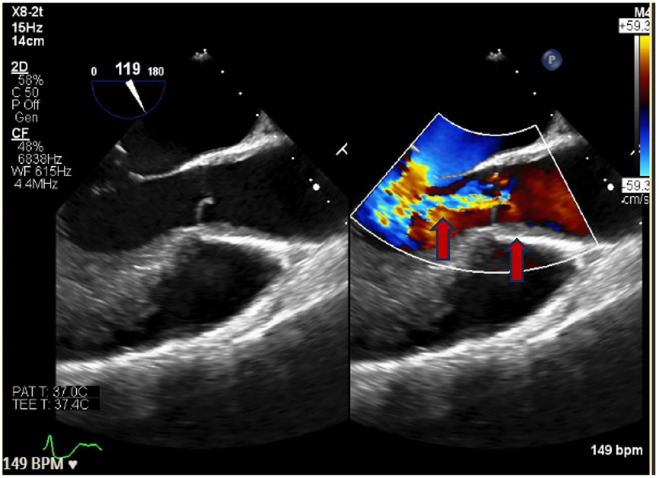

Takayasu's arteritis (TAK) is a rare, large-vessel vasculitis that typically involves the aorta and its major branches. Patients may experience coronary involvement, most commonly the left main coronary ostia. Patients with coronary artery occlusion often require emergent revascularization; however, there is debate regarding the optimal timing and type of surgical intervention in the setting of TAK. Herein we describe a 32-year-old female presenting with non-ST elevation myocardial infarction (NSTEMI) who underwent percutaneous intervention (PCI) with drug-eluting stent (DES) placement and was subsequently diagnosed with TAK. A 32-year-old female presented to the emergency department with chest pressure and dyspnea. Her electrocardiogram findings and troponin elevation were consistent with NSTEMI and she underwent coronary angiography with DES placement. During angiography, aortic insufficiency was noted. Transesophageal echocardiogram confirmed intimal thickening of the aortic root with aortic regurgitation. She was diagnosed with TAK, started on high-dose steroids, and transferred to a tertiary care center for rheumatology consultation. This patient's clinical course raised several questions regarding surgical intervention in TAK. The optimal timing of surgery and preferred approach (endovascular intervention vs coronary artery bypass grafting [CABG]) were specifically critiqued. While endovascular intervention (PCI with angioplasty or stent) is typically less invasive than CABG, it may be associated with a higher risk of postsurgical re-stenosis and studies are conflicting regarding the optimal approach. Further research is necessary to determine the long-term efficacy and safety of these interventions, as well as their timing in the overall management plan.